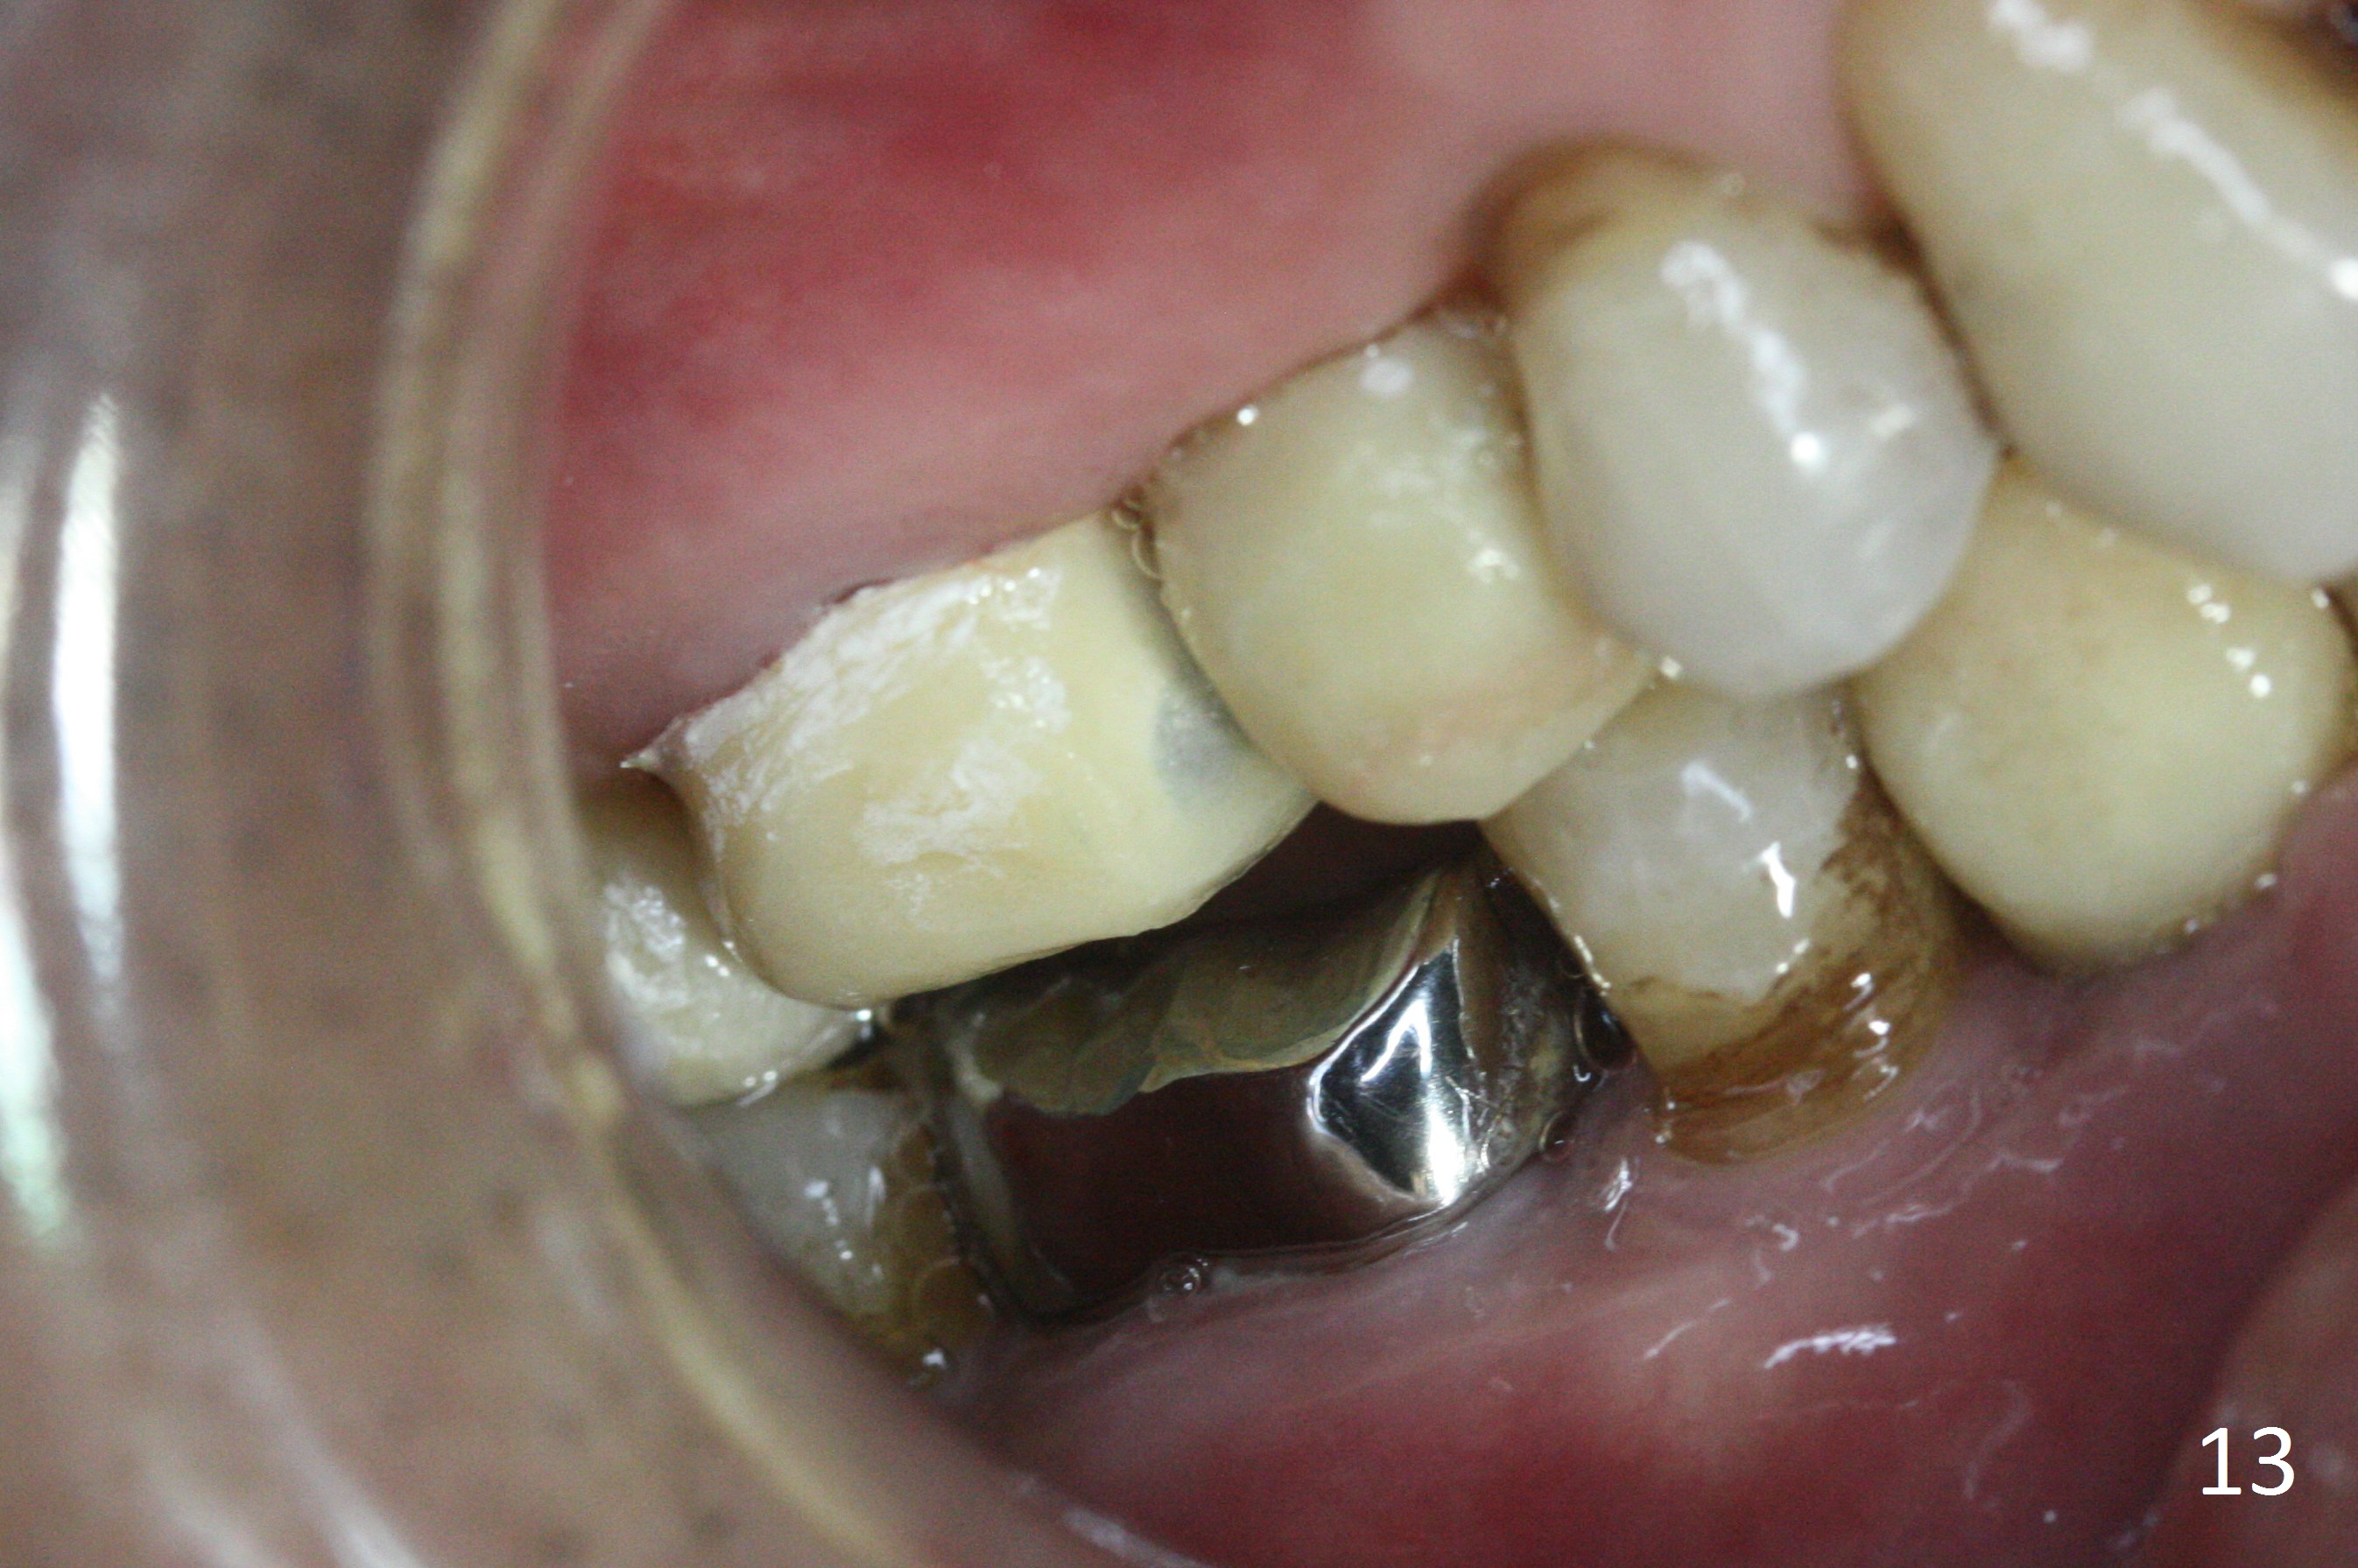

Six months postop, the upper right splinted provisional between #2 and 4 is sectioned so that the tooth #3 is also free to erupt naturally (Fig.13). The patient tolerates occlusal increase well.